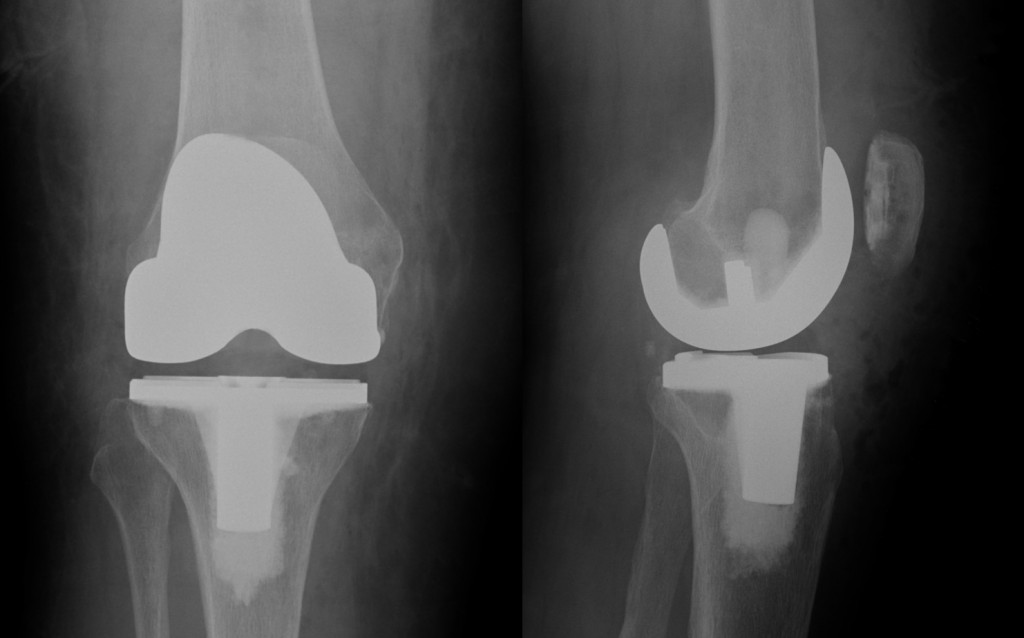

X-rays showing front (left image) and side (right image) views of a revision total knee replacement. The metal objects running down the front of the knee are surgical staples. Revision surgery may require extensive reconstruction and complex implants (compare to the images of a total knee replacement).